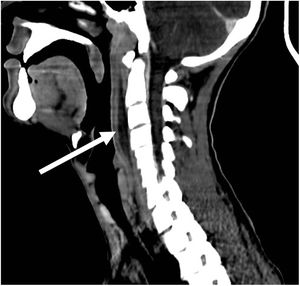

Se objetiva una colección laminar de 7,5×3,3×0,9cm, de paredes hipercaptantes, en espacio retrofaríngeo, extendiéndose desde C2 a C6 (fig. 1), y múltiples adenopatías laterocervicales bilaterales de aspecto reactivo (fig. 2). Con el hallazgo de posible absceso retrofaríngeo, se contacta con el servicio de otorrinolaringología, que decide ampliar el espectro de antibioterapia asociando meropenem y clindamicina, y manejo quirúrgico. Se realiza faringotomía posterior, con punción en diferentes puntos de la pared posterior, sin obtener material para cultivos.